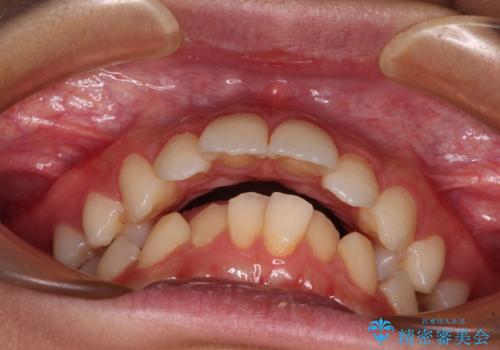

- 上顎前歯の突出感を気にして来院された患者様です。

舌の突出癖などにより、上下前歯の間に指が入るくらい隙間のできる状態でした。

下顎は叢生があったため、上下左右の第一小臼歯4本を抜歯し、更には口元の突出感を大きく改善させるために、上顎臼歯を後方に移動させるための補助装置をしようし、ワイヤー装置にて矯正治療を行うこととしました。